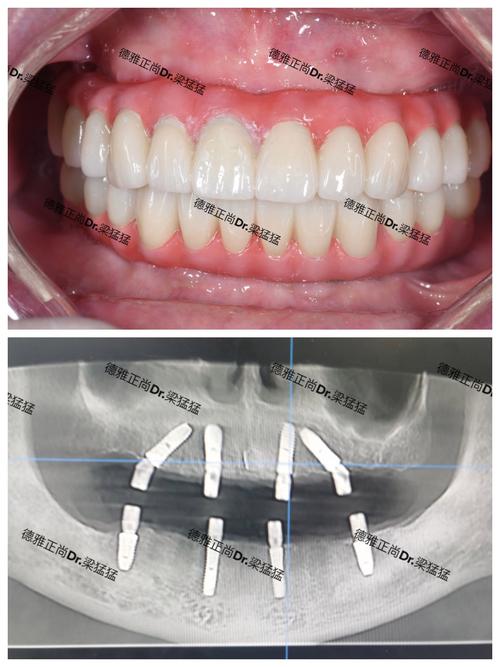

- All-on-4® 立即负重技术: 这是目前最主流、最常用的全口种植方案。仅需植入4颗种植体(上颌或下颌各4颗),后两颗种植体通常以一定角度植入,以避开重要的解剖结构(如下牙槽神经管、上颌窦),同时利用倾斜角度增加骨接触面积和抗旋转能力,从而用最少的种植体支撑起整个牙桥,实现当天或短期内戴牙(立即负重)。

- All-on-6 技术: 在骨量相对较好或希望获得更分散的咬合力分布时使用。植入6颗种植体(上颌或下颌各6颗),提供比All-on-4更多的支撑点,理论上长期稳定性可能更好,但费用更高,手术时间也可能稍长。

| All-on-4® | 4颗 | 骨量不足(尤其后牙区);追求性价比;希望尽快恢复功能 | 最主流方案;利用倾斜角度增加稳定性;可能当天戴牙;费用相对较低 |

| All-on-6 | 6颗 | 骨量尚可;希望获得更分散的咬合力;预算充足 | 比All-on-4多2颗种植体;提供更多支撑点;长期稳定性可能更好 |